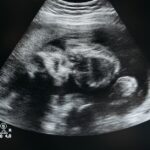

Au cours du premier trimestre, le bébé débute sa formation organique avec la différenciation des membres, le développement du système nerveux et un début de battement cardiaque visible lors de la première échographie, qui se déroule généralement autour de la 12e SA. Ce contrôle est crucial pour confirmer la viabilité de la grossesse et détecter d’éventuelles anomalies. En suivant avec attention ces rendez-vous, vous participez à assurer la meilleure stabilité pour le futur bébé.

Dans le second trimestre, la croissance s’accélère et le bébé devient plus actif. Des mouvements détectables par la maman se font sentir, accompagnés par l’apparition d’empreintes digitales et le développement auditif. L’échographie morphologique, effectuée entre 20 et 22 SA, évalue précisément la taille, les organes et la position du fœtus. Pour les mamans soucieuses de bien-être, c’est aussi l’occasion de découvrir les réactions du bébé aux stimulations extérieures, un moment magique relaté par de nombreuses mamans célèbres comme Audrey Tautou.

Enfin, le troisième trimestre est centré sur la maturation des systèmes vitaux en vue de la naissance. Le système respiratoire se développe, la prise de poids s’intensifie, et les séances d’échographie prénatale permettent un suivi rigoureux de la position du bébé et de la santé du placenta. Ce dernier trimestre implique aussi une vigilance accrue sur les signes annonciateurs de l’accouchement pour éviter toute urgence.